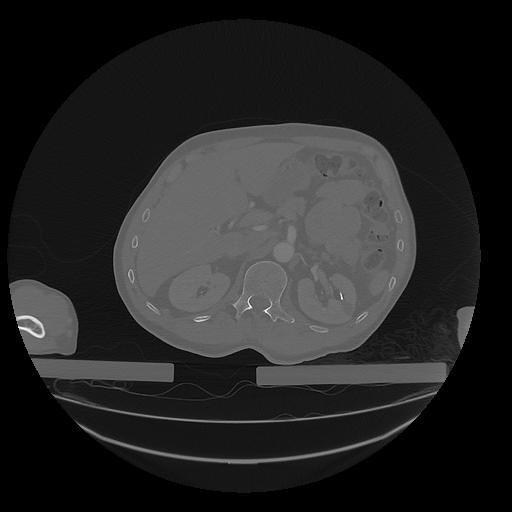

31 PULMON,CE,Vol,1.0,PULMON,,